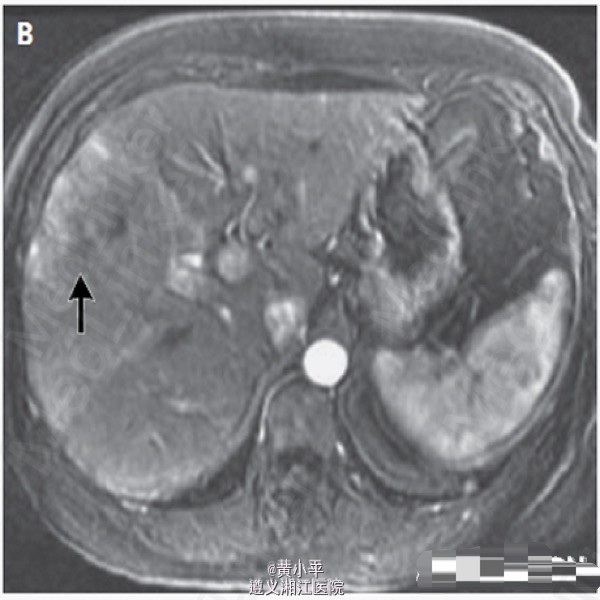

查体:BP190/97mmHg,其余生命体征正常。腹软,于右上腹可触及柔软肝脏边缘,未及肝脾肿大或腹胀。余查体正常。肝脏MRI增强发现右叶9.4cm×12.3cm×8.5cm异质性增强肿块。另有一处在第七段发现5mm病变,考虑可能为转移灶;余肝右叶多发小病灶考虑为血管瘤。(图1-3) 血浆皮质醇水平为23.5μg/dL(648 nmol/L)(参考值5-15μg/dL);血管活性肠多肽32pg /mL(参考值小于75)。入院第二天行SPECT,提示肝右叶大范围喷曲肽再摄取降低,符合MRI所示。